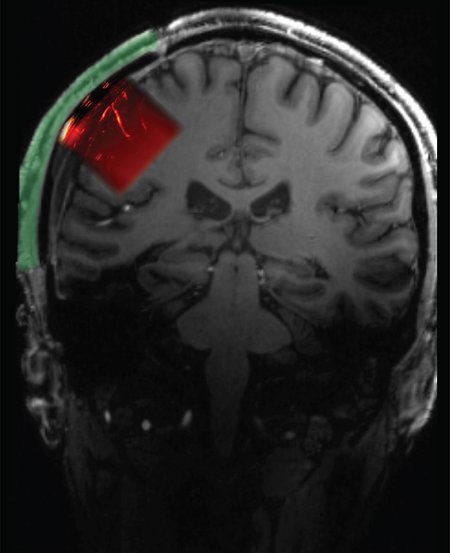

医療・健康 脳を覗く窓(A Window Into the Brain)